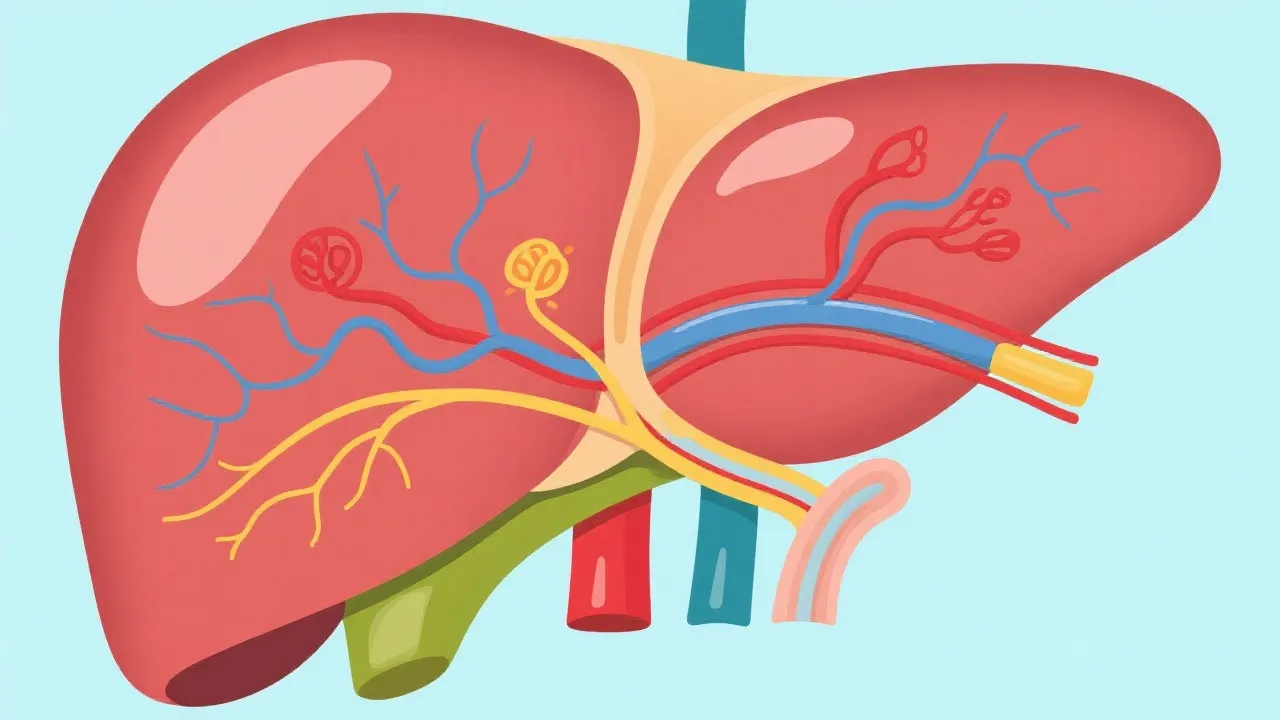

This article explores the role of Cyp2e1 in the pathogenesis of NAFLD, a chronic liver condition characterized by excessive fat accumulation in liver cells. Cyp2e1, an enzyme of the cytochrome P450 family, is known for its role in drug metabolism and bioactivation, but its involvement in fatty liver disease has garnered recent attention. Understanding the biochemical pathways can provide insights into potential therapeutic strategies for NAFLD.

Non-alcoholic fatty liver disease (NAFLD) is emerging as one of the very prevalent chronic liver diseases worldwide. Characterized by excessive fat accumulation in the liver, NAFLD can progress to more severe conditions such as non-alcoholic steatohepatitis (NASH), cirrhosis, and end-stage liver disease. Despite its increase globally, understanding the biochemical underpinnings of NAFLD has proven complex, with genetics, diet, and environmental factors all playing roles. The rapid rise in NAFLD cases has been linked to the growing prevalence of obesity and type 2 diabetes, which are salient health issues across various countries. As these metabolic disorders increase, so does the incidence of NAFLD, making it a significant public health concern that necessitates urgent attention and action.

NAFLD encompasses a spectrum of liver conditions, from simple steatosis, where excessive fat is deposited in liver cells, to more severe manifestations such as NASH, which is characterized by liver inflammation and damage. The distinction between these stages is critical because while simple steatosis may have a relatively benign course, NASH carries the risk of further progression to cirrhosis or even hepatocellular carcinoma. Statistically, approximately 25% of individuals with NAFLD progress to NASH, and about 20% of those may develop cirrhosis within a decade, underscoring the urgency of early detection and intervention. Understanding and recognizing the risk factors associated with these transitions is essential for preventing progression and enhancing liver health.

Cyp2e1 is part of the cytochrome P450 family, involved in the metabolism of various exogenous substances like drugs and toxic chemicals. In the liver, Cyp2e1 is critical for the bioactivation of small molecules, contributing to not only detoxification processes but also potentially to the activation of toxic intermediates. Emerging research suggests that Cyp2e1 may also play a pivotal role in NAFLD, primarily through its involvement in oxidative stress pathways. Specifically, its function includes the metabolism of alcohol, acetaminophen, and other xenobiotics, which results in the generation of reactive oxygen species (ROS), thereby implicating it in oxidative stress and inflammation that characterize liver damage in NAFLD.

The link between Cyp2e1 and NAFLD lies in its ability to produce reactive oxygen species (ROS) during metabolic processes. These ROS are known to cause oxidative damage to hepatocytes, the liver's main cell type, and can trigger inflammatory pathways. This oxidative stress and inflammation are key contributors to liver cell damage, exacerbating the progression from simple fatty liver to more severe liver conditions. Further compounding this issue is the fact that individuals suffering from obesity or those with metabolic syndrome usually present with increased levels of Cyp2e1 expression, suggesting its upregulation under conditions of metabolic dysregulation and lipid accumulation. The interplay between lipid metabolism and oxidative stress mediated by Cyp2e1 occupies a critical position in the pathogenesis of NAFLD.